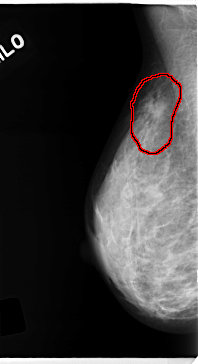

C_0139_1.RIGHT_MLO

RIGHT_MLO LINES 4720 PIXELS_PER_LINE 2568 BITS_PER_PIXEL 12 RESOLUTION 50 OVERLAY

FILE: C_0139_1.RIGHT_MLO.OVERLAY

TOTAL_ABNORMALITIES 1

ABNORMALITY 1

LESION_TYPE MASS SHAPE IRREGULAR MARGINS SPICULATED

ASSESSMENT 5

SUBTLETY 4

PATHOLOGY MALIGNANT

TOTAL_OUTLINES 1

BOUNDARY